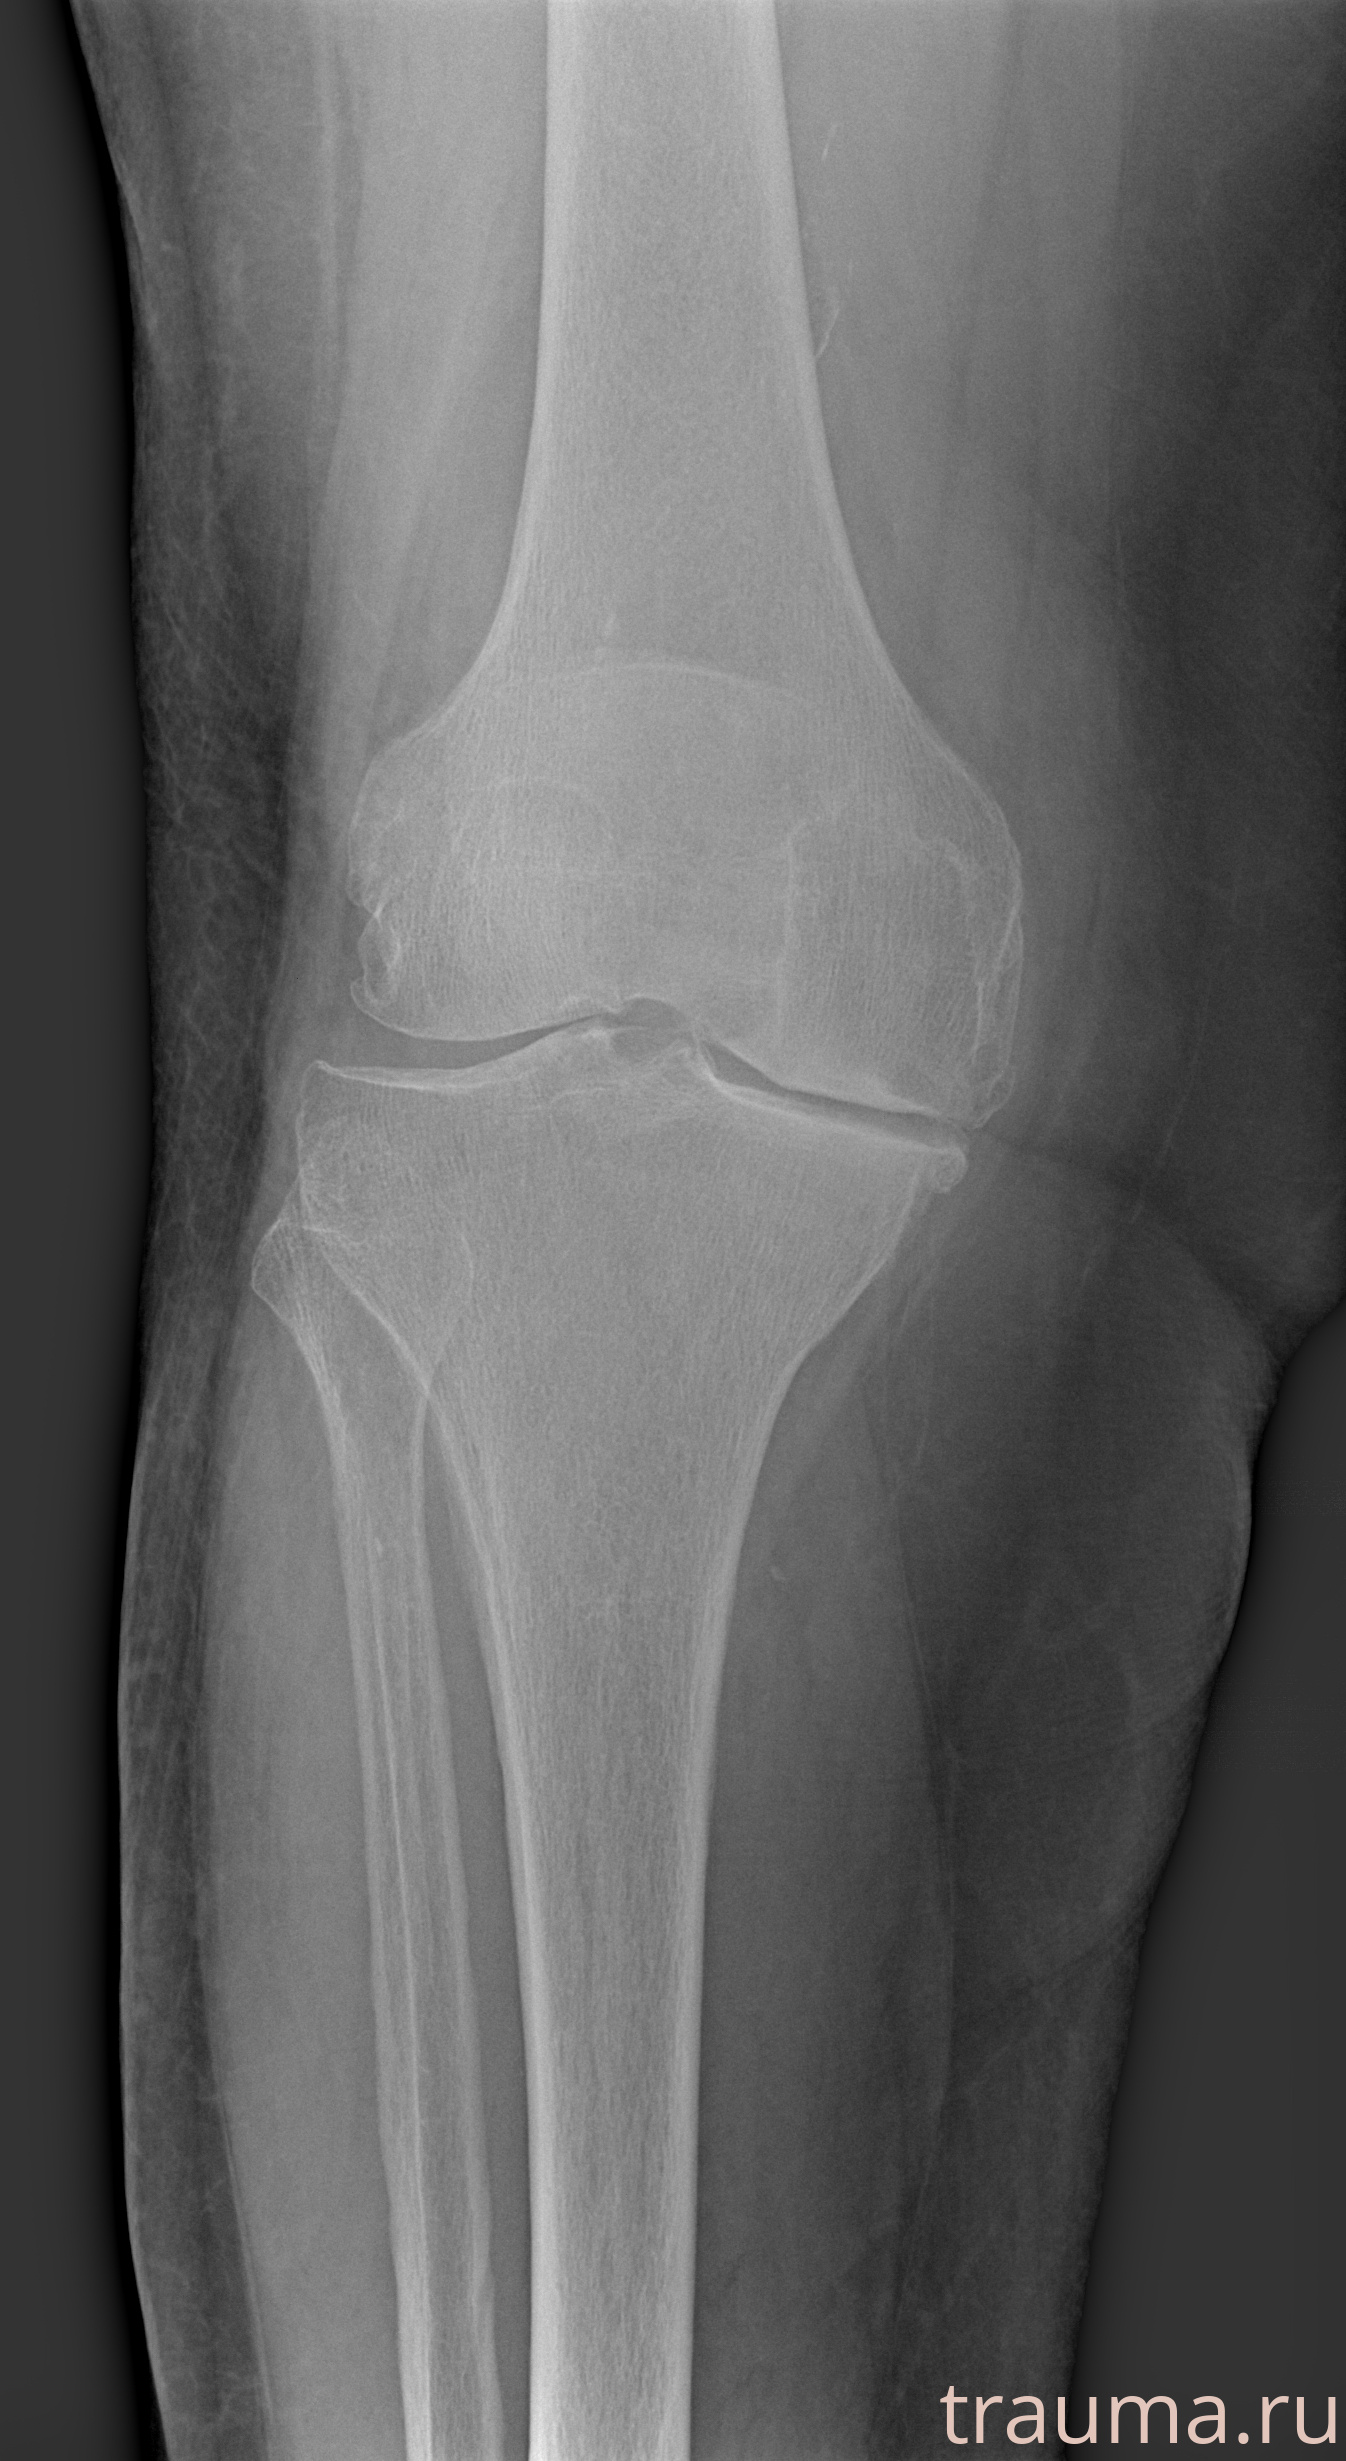

Рентгенограммы